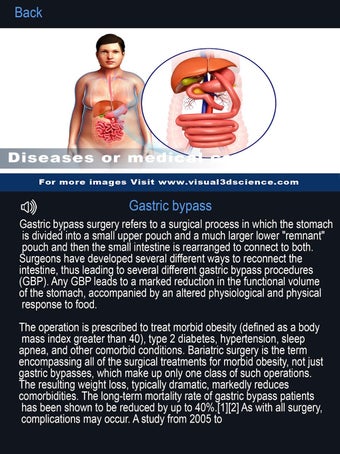

La interfaz fácil de usar de My Organs Anatomy permite una navegación sencilla, lo que facilita la selección, rayos X, ocultación y visualización de órganos individuales. La aplicación también incluye un modo de animación, opciones de búsqueda y un panel de información que proporciona información relacionada. Además, la aplicación ofrece pronunciación de audio para todos los términos anatómicos, e incluso los usuarios pueden dibujar o escribir en la pantalla y compartir capturas de pantalla.